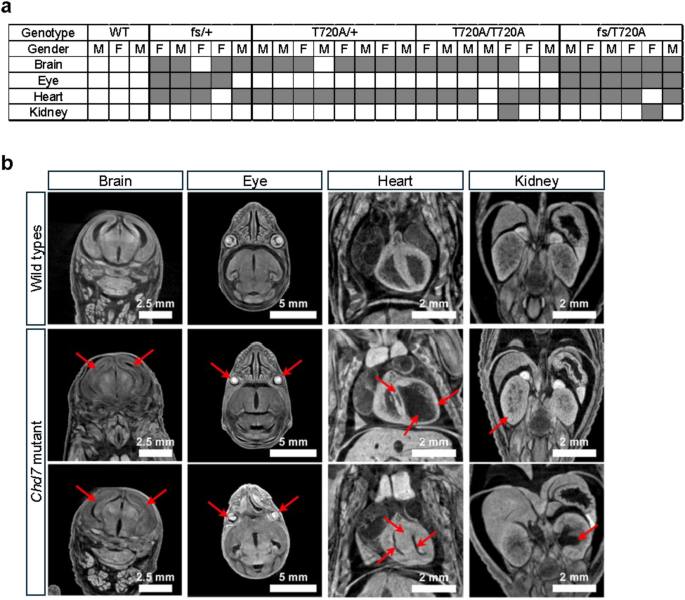

To further investigate these findings, we conducted a phenotypic analysis using micro-computed tomography (micro-CT) of E18.5 mouse embryos, allowing us to examine Chd7T720A/+, Chd7T720A/T720A, Chd7fs/+, and Chd7fs/T720A mice before viability loss. This analysis included assessments of gross morphological abnormalities, such as dysmorphisms, growth delays, edema, and craniofacial anomalies, as well as anatomical defects in major organs. Notably, the most pronounced and consistently observed abnormalities were found in the brain, eyes, and heart (Fig. 2a and b). We observed highly penetrant eye defects, including unfused eyelids and microphthalmia, in Chd7fs/+ and Chd7 embryos, suggesting a strong association with the Chd7fs allele. In contrast, all Chd7T720A/+ and Chd7T720A/T720A embryos had normal eyes. In the brain, reduced lateral ventricle size was observed across most mutant genotypes. These findings corroborate previous research on CHD7 haploinsufficiency, with the Chd7fs allele phenotypes closely aligning with the Chd7COA1/+mouse model carrying the K719X nonsense mutation17.

We also observed highly penetrant heart abnormalities in both male and female mice carrying Chd7fs and Chd7T720A alleles (Fig. 2b). Micro-CT section analysis revealed embryos carrying these alleles exhibited both enlarged and reduced ventricular chambers compared to WT embryos. Embryos with enlarged ventricular chambers displayed thinning of the ventricular walls, characteristic of DCM. In contrast, embryos with reduced ventricular chambers showed thickened ventricular walls and septa, consistent with HCM. Additionally, two of the Chd7fs/+embryos (one male and one female) exhibited a ventricular septal defect (VSD), a hallmark in CHARGE syndrome and its mouse models16,18, characterized by a discontinuous gap in the ventricular septum. Interestingly, these embryos also showed enlarged ventricular chambers, consistent with a DCM-like phenotype. Given that CHD7 functions as a chromatin remodeler involved in cardiac development, its haploinsufficiency may disrupt transcriptional programs required for myocardial homeostasis. This could contribute to chamber dilation through mechanisms involving cardiomyocyte survival, extracellular matrix remodeling, or altered contractility. In more severe cases, progressive myocardial thinning may further impair ventricular septation, ultimately leading to VSD. The presence of VSD in some, but not all, Chd7fs/+ embryos suggests that while these defects may arise through overlapping mechanisms, they are not necessarily linked in all cases. Further studies will be necessary to elucidate the precise relationship between CHD7 function, myocardial development, and ventricular septation. Notably, this ventricular septal defect was not observed in mice carrying the Chd7T720A allele.

Gross morphology and 2D digital section phenotyping with iodine-contrasted micro-CT. (a) Table summarizing the occurrence of organ abnormalities in Chd7 mutants across different genotypes: WT (Chd7+/+), T720A/+ (Chd7), T720A/T720A (Chd7T720A/T720A), frameshift null fs/+ (Chd7fs/+), and compound heterozygous fs/T720A (Chd7fs/T720A). The analysis was performed on mouse embryos at embryonic day 18.5 (E18.5) using micro-CT. Shaded areas in the table indicate the presence of abnormalities in various organs including the brain, eye, heart, and kidney. (b) Representative micro-CT images showing the phenotypic abnormalities observed in Chd7 mutants. The abnormalities are indicated by red arrows and are organized by organ: Brain (reduced lateral ventricular size in Chd7T720A/+ and Chd7fs/T720A mutants), eye (microphthalmia observed in two Chd7fs/+ mutants, heart (enlarged ventricular chamber, thinning of the ventricular wall, and ventricular septal defect in Chd7fs/+ mutant; or reduced ventricular chamber and thickened ventricular wall in Chd7fs/T720A mutant), and kidney (enlarged kidney in Chd7T720A/T720A mutant; or hydronephrosis in Chd7fs/T720A mutant). Scale bars for reference are included in the images (2.5 mm, 5 mm, and 2 mm).